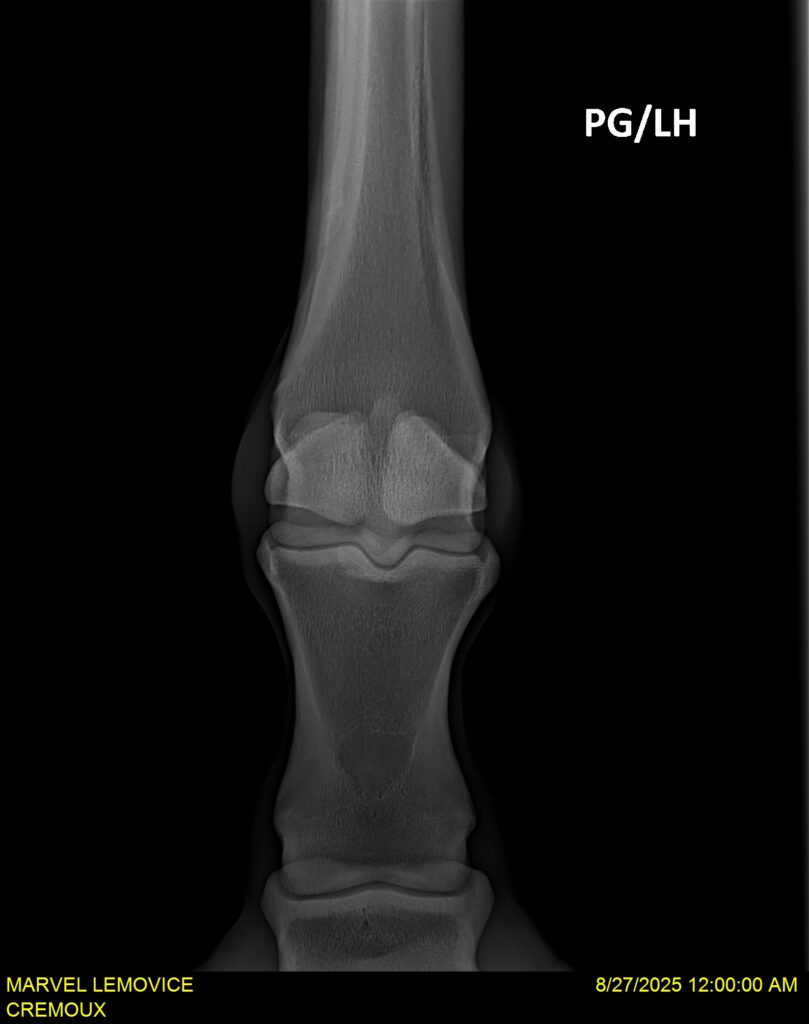

MARVEL LEMOVICE, hongre, Selle Français prend 4 ans en 2026. POPSTAR LOZONAIS x ROSIRE sur une excellente souche maternelle de l’élevage PLATIERE. Débourré aux trois allures et mise en route à l’obstacle. Super modèle avec du cadre et de la force, cheval respectueux avec des moyens. Très agréable au quotidien. Transport OK, maréchalerie OK, santé RAS, Bilan 20 clichés radios + clinique OK.

RADIOS ET CLINIQUE